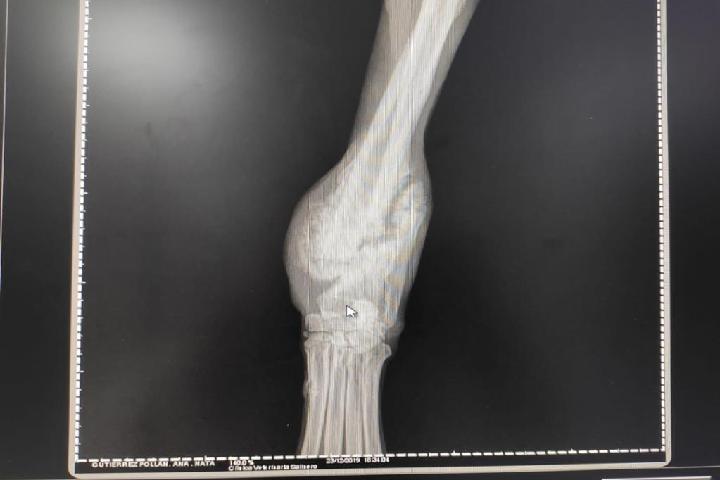

Nata, asi le hemos llamado a una galguita rescatada del abandono, soledad, miseria de las calles de salamanca. Son muchos meses detrás de ella, sopesando cada día el sacarla de las calles. Lo hemos conseguido, pero el estado de su patita delantera es muy fea, una pata fracturada por completo y hecho callo sobre dicha fractura. Necesitamos operarla para darle la calidad de vida que se merece y darle el hogar que tanto merece. La operación cuesta aprox 1000€ y necesitamos ayuda para costearla.